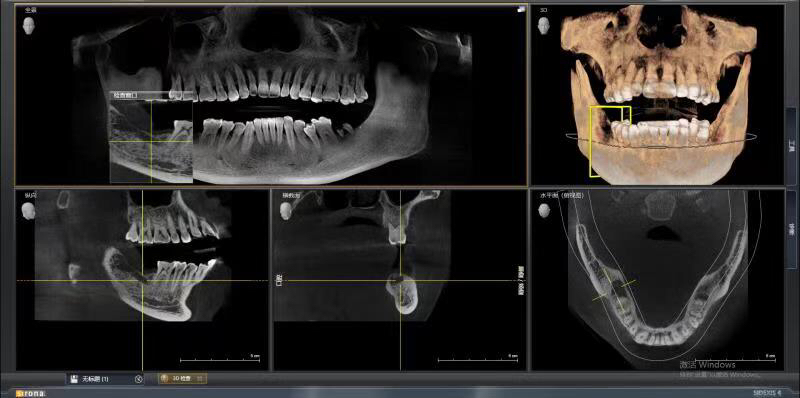

患者中年男性,右下7号牙龋坏未及时处理至残根无法修复,CT检查发现骨量尚可,可以即拔即种,并且不需要植骨,节省了患者治疗周期,整个治疗过程用了4个月患者就戴上了牙齿。